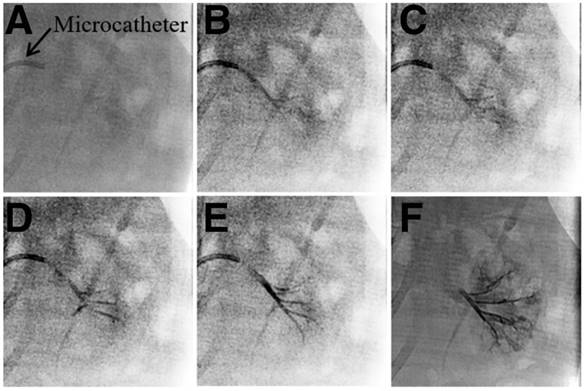

Figure 5

DSA images of left kidneys of rabbits (A) before, (B) immediately after and (C) 4 weeks after embolization by Ta@CaAlg microspheres.

The in vivo embolic effect of Ta@CaAlg microspheres was also evaluated by the standard method of re-examination, that is DSA, after the TACE procedure. DSA can clearly visualize blood vessels by subtracting a “pre-contrast image” from the subsequent image of the same area after introduction of contrast medium. In order to super-selectively catheterize, Iodixanol solution was first injected prior to embolization to reveal the blood vessel. A DSA image of a normal rabbit kidney immediately after injection of Iodixanol is shown in Figure 5A. All levels of the renal arteries could be observed, indicating that the blood vessels were empty and could be filled by the contrast medium. Immediately post-embolization of the left renal artery with Ta@CaAlg microspheres, Iodixanol was injected again to evaluate the embolic effect. In the DSA image in Figure 5B, the left kidney disappeared, suggesting that the renal arteries in the left kidney were totally embolized by the Ta@CaAlg microspheres. This meant that the contrast media could not diffuse into the embolized kidney and instead refluxed to the unblocked blood vessels of the right kidney. After 4 weeks of embolization, the DSA image in Figure 5C was the same as that in Figure 5B, indicating that the left renal artery was still firmly embolized. As shown in Figure S7, the blank calcium alginate microspheres produced a similar embolic effect. These DSA images demonstrate that vascular recanalization did not occur after the embolization by Ta@CaAlg microspheres, suggesting that Ta@CaAlg microspheres produce an excellent embolic effect.